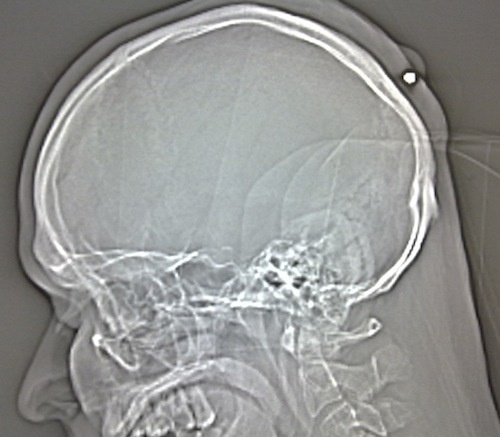

Man Finds Out He Was Shot in the Head Five Years After the Fact

A man who was shot in the back of the head with a .22 caliber bullet five years ago recently just discovered the fact during a check-up with his doctor: He found a lump in the back of his head which, upon examination by x-ray (above), turned out to be the bullet.